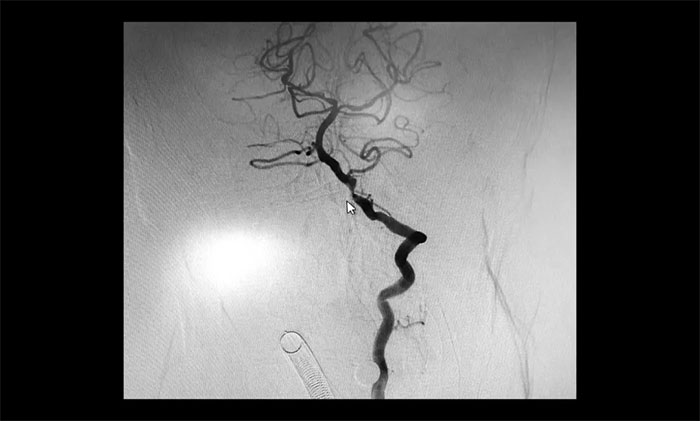

▲ 术后,左侧颈内动脉狭窄明显改善

术后康复观察一月余,于耀宇主任团队再次为曹老伯行右侧颈动脉支架置入及左侧椎动脉支架置入手术。术中造影显示,右侧颈内动脉起始段重度狭窄,狭窄长度8mm左右。左侧椎动脉 V4 段重度狭窄,长度6mm左右。运用娴熟扎实的技术,在充分做好脑保护的前提下经过多次球囊扩张后,顺利释放支架于狭窄处。造影提示支架打开良好,血管狭窄基本恢复正常,支架贴壁佳,支架内血流通畅,远端血流良好。

▲ 术后,右侧颈内动脉及左侧椎动脉狭窄明显改善